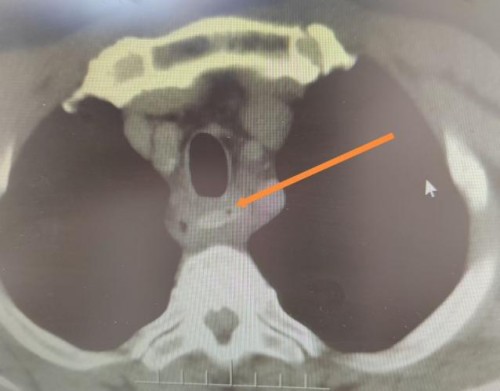

当天下午三点,王先生就诊北京中西医结合医院耳鼻咽喉头颈外科。接诊的赵龙珠主任迅速判断病情危急,立即安排肺部CT检查。影像结果令人揪心:枣核仍然卡在食管中段,更危险的是,CT显示纵隔已有少量积气——这意味着尖锐的枣核很可能已经刺穿食管壁,造成了食管穿孔!

“食管穿孔不及时处理可能导致纵隔感染、脓胸甚至败血症,死亡率很高。”赵龙珠主任面色凝重地解释道。然而,棘手的问题摆在面前:枣核位置较深,超出了耳鼻咽喉头颈外科常规支撑喉镜的可视范围。危急关头,赵龙珠主任立即联系脾胃病科主任王韶华、副主任医师林栋雷。一场与时间赛跑的救援就此展开。